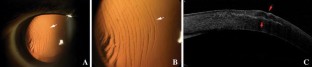

A 45-year-old woman presented with a traumatic laser-assisted in situ keratomileusis (LASIK) flap dislocation in the right eye. Anterior segment optical coherence tomography (OCT) showed the presence of macrostriae, flap stromal edema, epithelial hyperplasia between the striae and epithelial ingrowth. The flap was surgically repositioned with optimal visual recovery. Anterior segment OCT can efficiently visualize corneal structural changes associated with LASIK flap dislocation.

Fig. 1